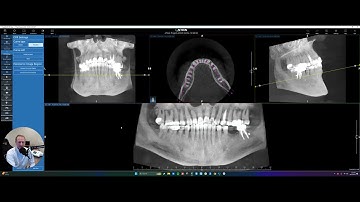

RealGUIDE Software: Curve Planner Reformation (CPR) Settings